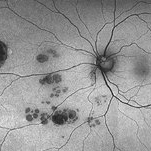

Bear Tracks

Apr 27 2018 by Giselle DeOliveira

Fundus Montage photograph of 13-year-old girl.

Photographer: Giselle DeOliveira, University of Miami , Bascom Palmer Eye Institute

Condition/keywords: bear tracks